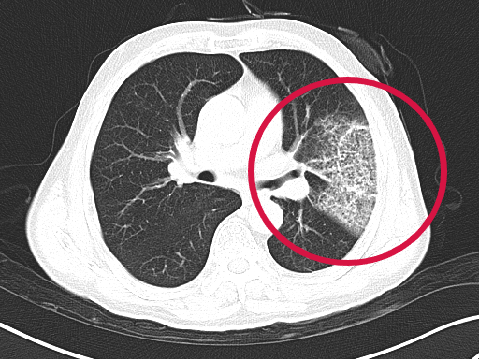

第二根消融針置入并開始消融

▲患者因體檢發(fā)現(xiàn)左肺上葉舌段結(jié)節(jié),考慮周圍型肺癌可能。因高齡、肺氣腫無法手術(shù),遂來院接受肺結(jié)節(jié)冷凍消融治療,術(shù)后病理為肺癌,定期隨訪提示腫瘤逐漸縮小。